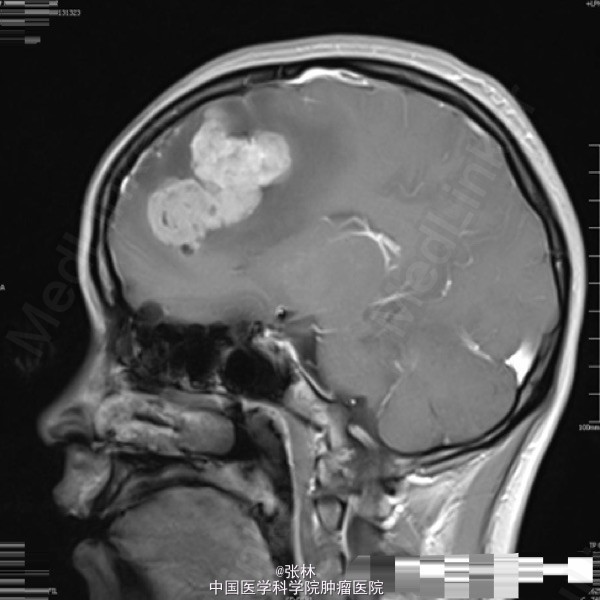

42岁女性,10余天前无明显诱因出现头痛,并呕吐胃内容物,双眼视物模糊。影像学表现:右侧额叶见一不规则形占位性病变,大小约为3.7×4.0×4.5cm,T1WI呈等、低信号,T2WI呈等、高信号,DWI仍呈高信号,周围脑组织少量水肿,增强扫描后病变呈明显强化,边缘水肿无强化。 病理: 镜检:肿瘤细胞弥漫增生,呈乳头状、腺样,细胞核卵圆形,深染。 免疫组化示:GFAP(散在细胞+)、Vimetin(+)、S100(-)、CK(+)、EMA(+)、ki-67(5%+)、CD99(部分+)、CD56(+)、NF(-)、CD34(-)、Hepa(-)、AFP(-)、mammaglobin(-)、RCC(-)、WT-1(-)、CD10(-)、CK7(-)、CK20(-)、Villin(-)、CR(-)、MC(-)、MOC31(-)。及少许脂肪组织,上皮混合组成。 讨论: 室管膜瘤来源于脑室与脊髓中央管的室管膜细胞或脑内白质室管膜细胞巢的中枢神经系统肿瘤。在胶质瘤中占6%,男多于女,多见于儿童及青年,约75%位于幕下,幕上仅占25%。文献报道幕上室管膜瘤75 ~85 %位于脑室外。脑实质内室管膜瘤起源于室管膜细胞嵴,可能是神经管内折叠时形成畸形的结果,好发部位为丘脑,其次为额叶、颞叶、顶叶。实性多见于成人,囊性多见于青少年。 幕上室管膜瘤以头痛、呕吐、嗜睡、厌食及复视等颅高压症状为主,多有局部运动功能障碍和癫痫。